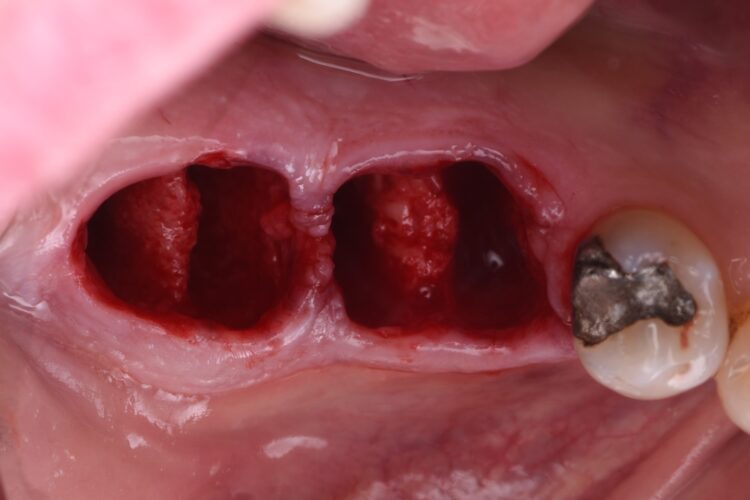

The failing teeth were sectioned and extracted atraumatically to preserve the surrounding bone. The sockets were thoroughly debrided using Lucas curettes to remove any residual infection or granulation tissue.

Dental implants were then placed using the sleeveless surgical guides. The guided kit from CONELOG® is fantastic, as the screw-in carriers allow for very accurate positioning. After verifying the implant placement, the carriers are replaced and can be used to maintain patency of the implant opening while the graft material is packed into the site.

MinerOss® Putty allograft (BioHorizons Camlog) is routinely selected for these cases. The handling properties are exceptional, making placement easy. Additionally, due to its 10% collagen composition, integration is exceptional, avoiding the ‘popcorn’ effect seen with other materials. The graft material was packed to the bone level, again to reduce the build-up of graft material in the soft tissue.